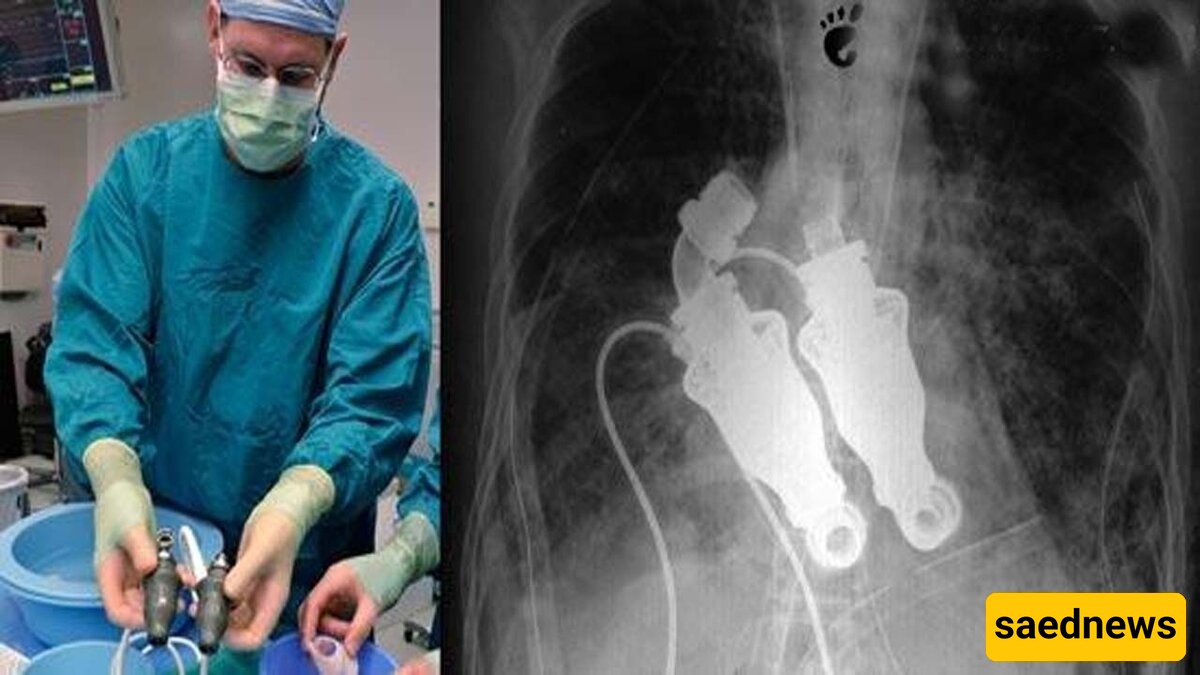

اقترح الدکتور بیلی کوهین والدکتور باد فریزر على عائله کریغ إزاله قلبه وزرع جهاز یقوم بتدویر الدم دون أی نبض للقلب. وافق کریغ لویس، وحافظ هذا الإجراء على حیاته. وکانت القصه مذهله لدرجه أن المخرج جیریمی زاغار، المرشح لجائزتی إیمی عام 2010، وثّق حیاه أول إنسان بلا قلب بتفاصیل کامله.

تدهورت حاله کریغ لویس یومًا بعد یوم، ما جعل الأطباء یشعرون بقلق متزاید. وکان على بعد وقت قصیر من الموت. وبعد سماع اقتراح الدکتورین کوهین وفریزر، اضطرت عائله کریغ لاتخاذ قرار سریع. فی مارس 2011، وافقت زوجته، مما سمح للأطباء بإزاله قلبه وزرع الجهاز.

یعمل الجهاز المزروع فی صدر کریغ مثل التوربین، حیث یدفع الدم فی جسده. یستخدم مکونات عریضه تشبه الشفرات لتدویر الدم دون أی حرکه ضخ. وبینما یمتلک بعض المرضى، بما فی ذلک نائب الرئیس الأمریکی السابق دیک تشینی، أجهزه مشابهه، إلا أن تلک الأجهزه عادهً تساعد إحدى بطینَی القلب فقط، ولا تحل محل القلب بالکامل.